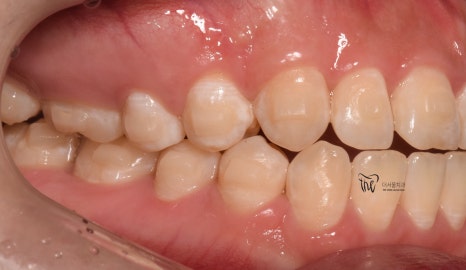

『치료 종료』

그리고, 다른 환자들과는 다르게

정기검진을 할 필요가 없었죠?

매일 보니깐요.

즉, 저와 늘상 가깝게 지내면서 치열의

변화를 같이 지켜봤으며 인비절라인

치아교정 치료를 이어나간 결과

이제 윗니가 아랫니를 겹치게 덮는 모양이

나오게 되면서 치료를 끝마치게 되었네요.

물론, 해당 교합관계는 재발이 잘 되기 때문에

시간이 오래 흘렀을 때도, 꾸준히 검진을

받으면서 관리를 받아야 됩니다.

그러면서, 어느 단계에서부터 턱관절 통증 및

뻐근함이 거의 다 사라졌다는..

이것은, 두마리 토끼를 같이 잡았다.^^

치료 기간 2021.01.03 ~ 2022.05.01